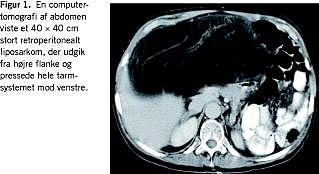

I. En 70-årig kvinde blev henvist til onkologisk behandling i juli 2003 pga. et 40 × 40 cm stort, inoperabelt LPS. Patienten havde haft utilsigtet vægtøgning og en fornemmelse for oppustethed i toethalvt år. Gastroskopi, ultralydskanning og koloskopi × 3 viste alle normale forhold, idet man dog fandt divertikulose i colon. Patientens symptomer blev tolket som colon irritabile og habituel vægtøgning. Efter ønske fra patienten blev der senere foretaget computertomografi (CT) af abdomen, og på CT'en sås en meget stor retroperitoneal tumor. Der blev foretaget laparotomi på et lokalsygehus, og patienten blev der vurderet til at være inoperabel. En peroperativ biopsi viste et højt differentieret LPS. Efter seks serier kemoterapi med doxorubicin fik patienten tiltagende tryksymptomer, og ved CT fandtes objektiv progression af tumoren. Patienten blev henvist til kirurgisk revurdering. Der blev udført en radikal excidering af en 40 × 40 cm stor retroperitoneal tumor, vægt 5.870 g. Tumoren udgik fra højre flanke og pressede tarmsystemet mod venstre (Figur 1 ). Det postoperative forløb var ukompliceret. Patienten blev fulgt med kvartårlige billeddiagnostiske undersøgelser og var ved seneste magnetiske resonans (MR)-skanning to år efter operationen recidivfri.